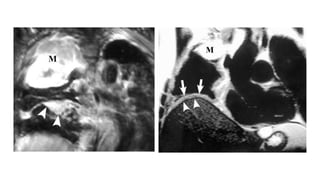

Resonancia magnética

• Se debe realizar RM en aquellos casos en los que la TAC con contraste esté

contraindicada o cuando la infiltración extrapleural no se demuestre

claramente con esta técnica.

• La RM es especialmente útil en los casos en que la enfermedad sea

potencialmente resecable y nos puede proporcionar información adicional

sobre el estado de los márgenes tumorales y la afectación del diafragma,

fascia y pared torácica.

HALLAZGOS EN LA RM

• Pérdida de los planos grasos

• Afectación circunferencial de más de 50% de las estructuras mediastínicas

• Afectación de la grasa mediastínica

• Invasión del diafragma

• Invasión de la fascia endotorácica

T1=================Isotenso o discretamente hiperinteso

T2=================Moderadamente hiperintenso

T1 + Gadolinio=======Realce intenso